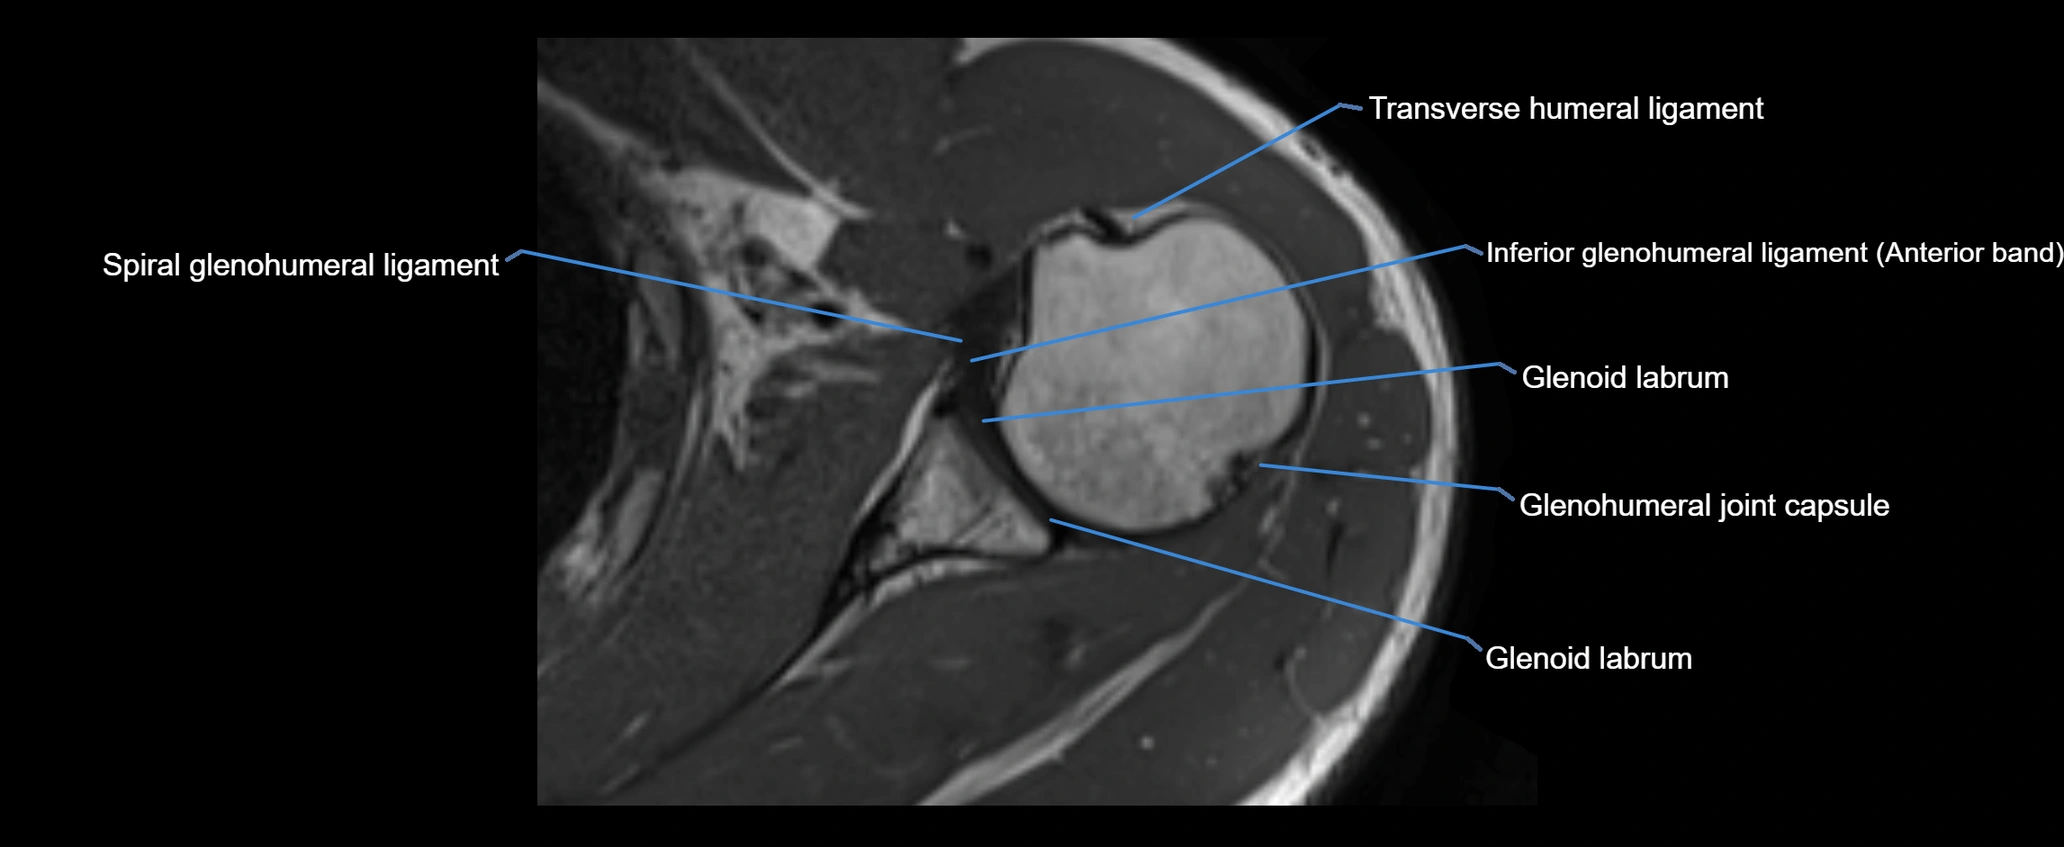

MRI images

image

MRI Appearance

• T1-weighted images:

• Normal ligament: Low signal (dark linear band) spanning acromion to clavicle.

• Surrounding fat planes: Bright, delineating the ligament clearly.

• Marrow of clavicle and acromion: Bright due to fatty content.

• Tears: Discontinuity or irregular thickening with intermediate-to-bright signal.

• Chronic injury: Thinning, fraying, or irregular low-signal fibers with adjacent scarring.

• T2-weighted images:

• Normal ligament: Low signal, homogeneous.

• Partial tear or sprain: Focal hyperintensity or thickening.

• Complete tear: Discontinuity with fluid-bright gap between clavicle and acromion.

• Associated edema: Bright signal in distal clavicle or acromion marrow.

• STIR:

• Normal ligament: Dark linear band.

• Injury or inflammation: Bright hyperintense signal in and around ligament fibers.

• Highlights periligamentous soft-tissue edema, especially in acute trauma.

• Proton Density Fat-Saturated (PD FS):

• Normal ligament: Low signal, uniform thickness.

• Partial tear or sprain: Bright signal or contour irregularity.

• Complete tear: Clear discontinuity with bright signal gap and joint effusion.

• Excellent for assessing joint capsule, coracoclavicular ligaments, and periarticular edema.